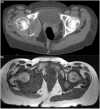

The purpose of this article is to familiarize the reader with the anatomy of the major pelvic nerves and the clinical features of associated lumbosacral plexopathies. To demonstrate this we illustrate several cases of malignant lumbosacral plexopathy on computed tomography, magnetic resonance imaging, and positron emission tomography/computed tomography. A new lumbosacral plexopathy in a patient with a prior history of abdominal or pelvic malignancy is usually of malignant etiology. Biopsies may be required to definitively differentiate tumour from posttreatment fibrosis, and in cases of inconclusive sampling or where biopsies are not possible, follow-up imaging may be necessary. In view of the complexity of clinical findings often confounded by a history of prior surgery and/or radiotherapy, a multidisciplinary approach between oncologists, neurologists, and radiologists is often required for what can be a diagnostic challenge.